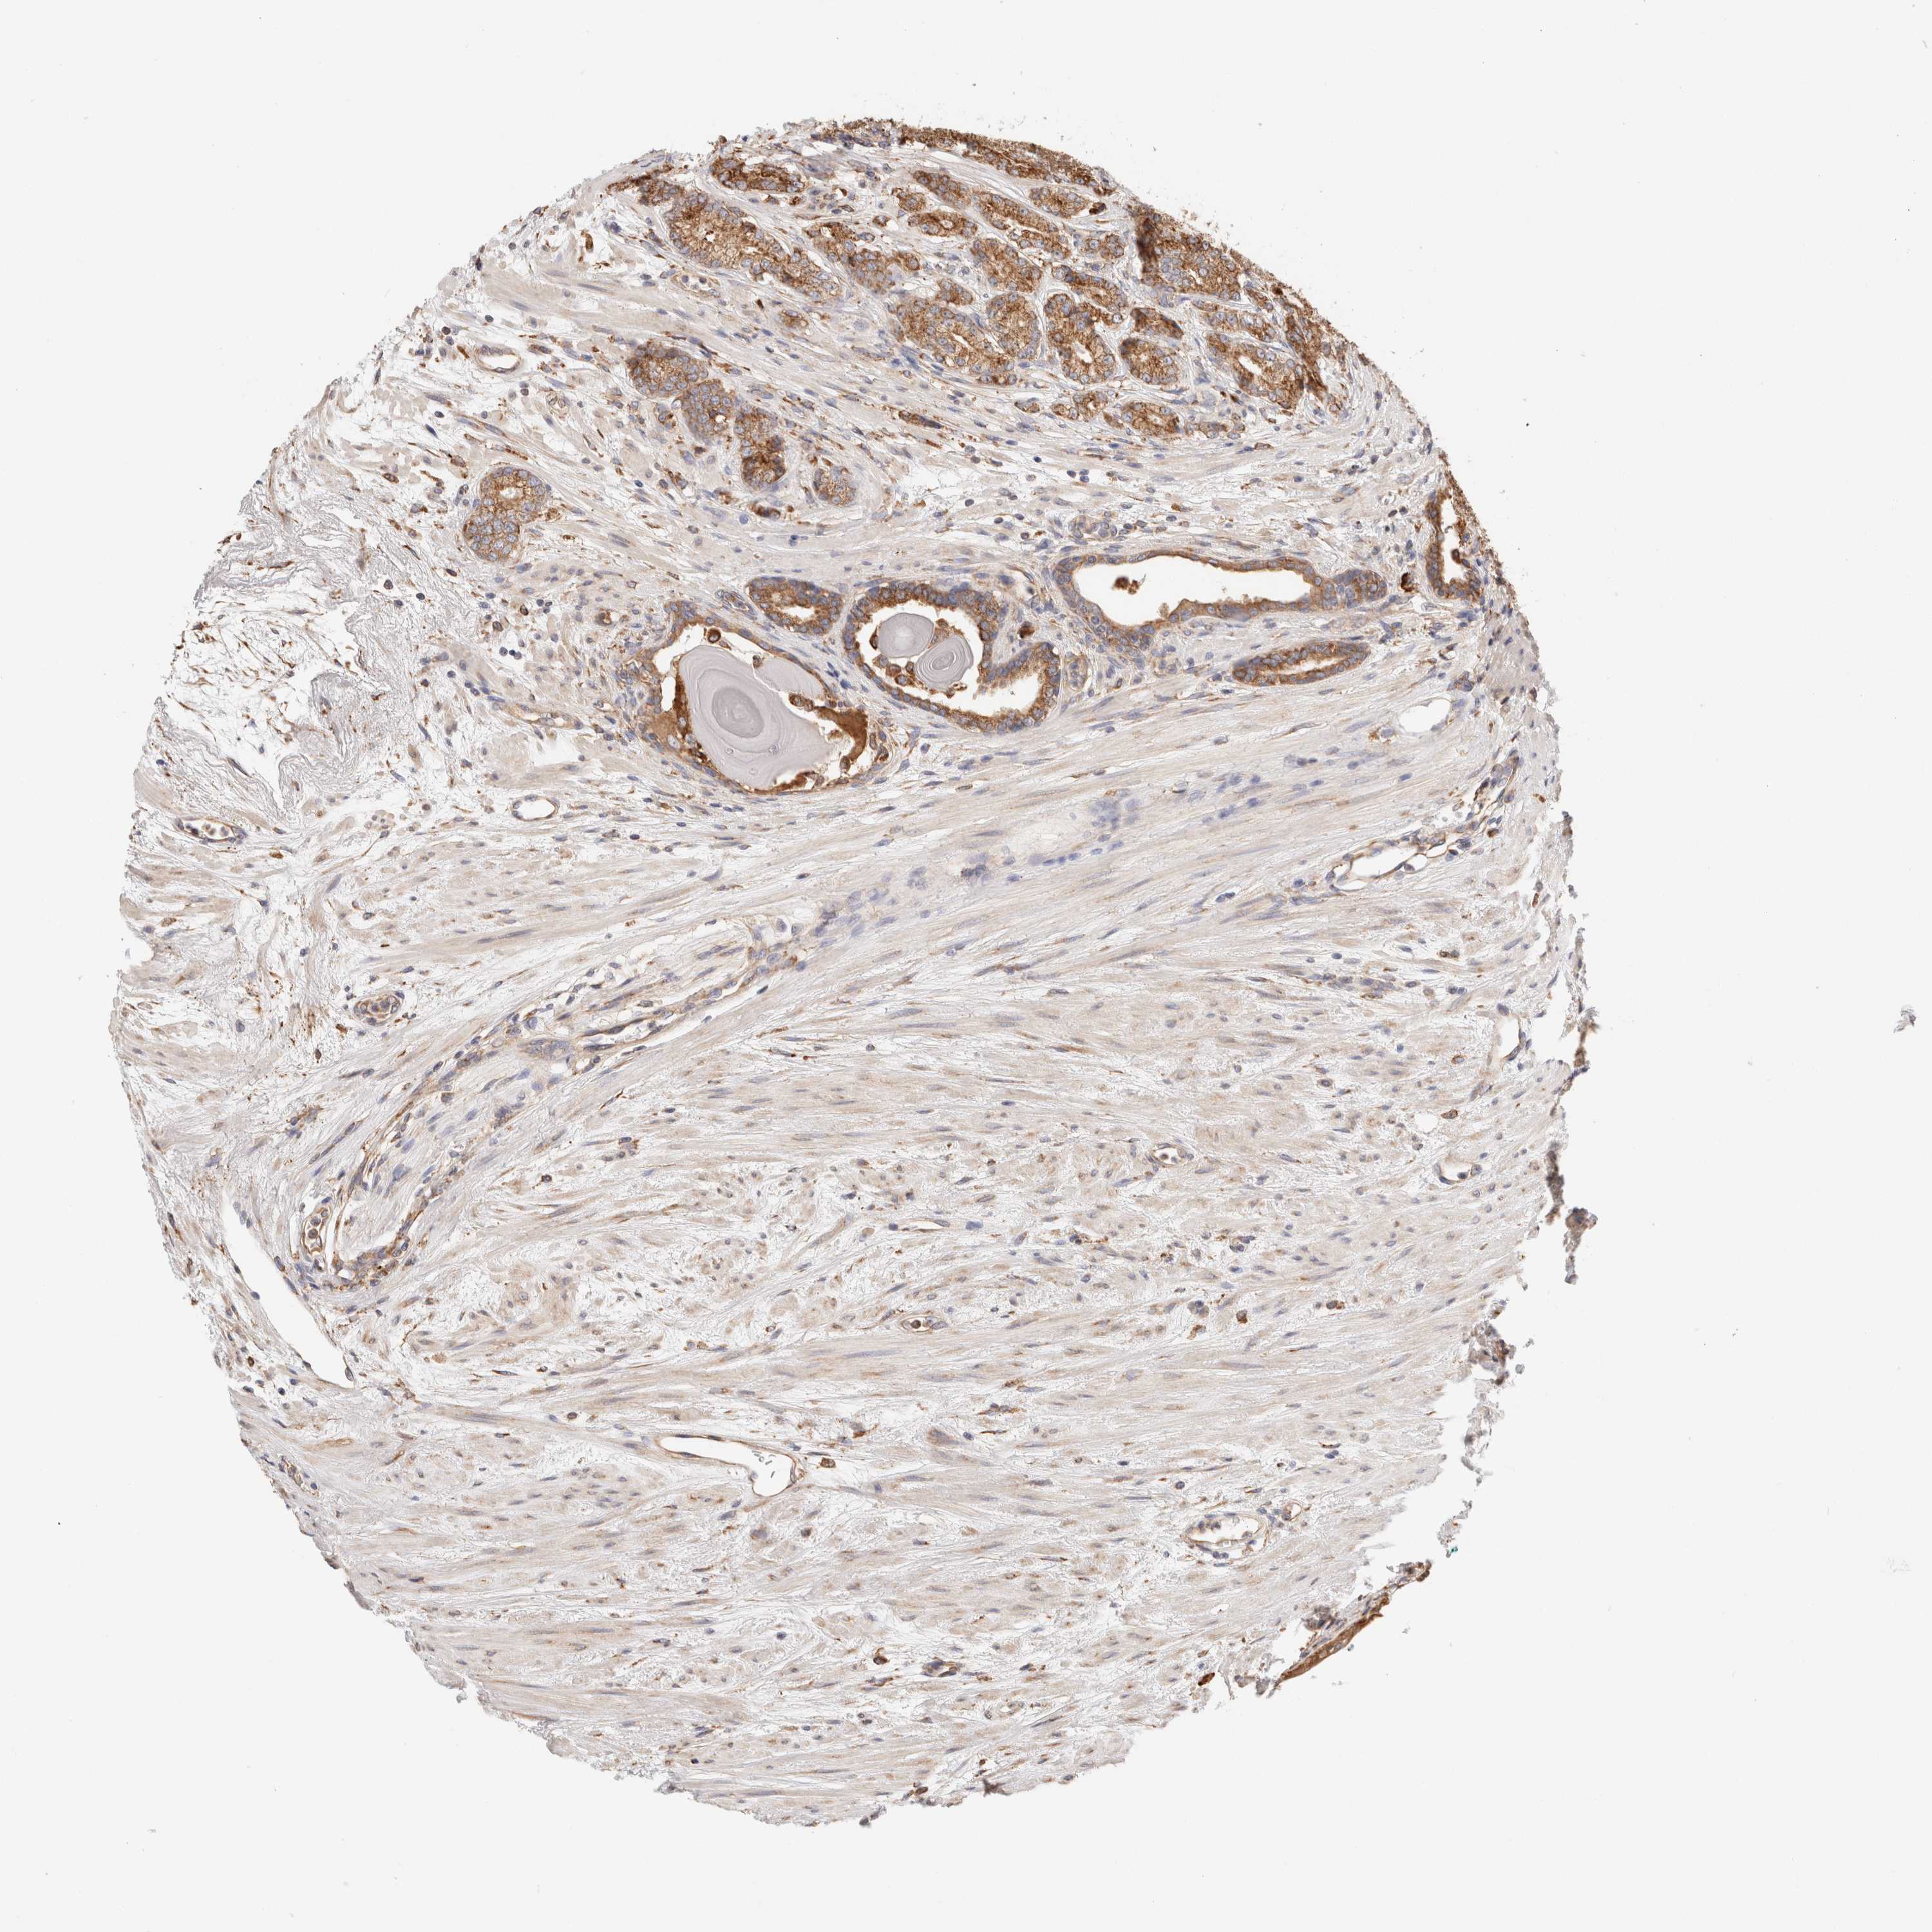

PROSTATE CANCER - Protein expressioni

A mouse-over function shows sample information and annotation data. Click on an image to view it in a full screen mode. Samples can be filtered based on level of antibody staining by selecting one or several of the following categories: high, medium, low and not detected. The assay and annotation is described here.

Antibody stainingi

Antibody staining in the annotated cell types in the current human tissue is reported as not detected, low, medium, or high, based on conventional immunohistochemistry profiling in selected tissues. This score is based on the combination of the staining intensity and fraction of stained cells.

Each image is clickable and will lead to virtual microscopy that enables deeper exploration of all samples and also displays staining intensity scores, fraction scores and subcellular localization as well as patient and tissue information for each sample.

Antibody HPA007641

Antibody CAB022464

Staining

High

Medium

Low

Not detected

Intensity

Strong

Moderate

Weak

Negative

Quantity

>75%

75%-25%

<25%

None

Location

Nuclear

Cytoplasmic/membranous

Cytoplasmic/membranous,nuclear

Adenocarcinoma, Low grade

Adenocarcinoma, High grade